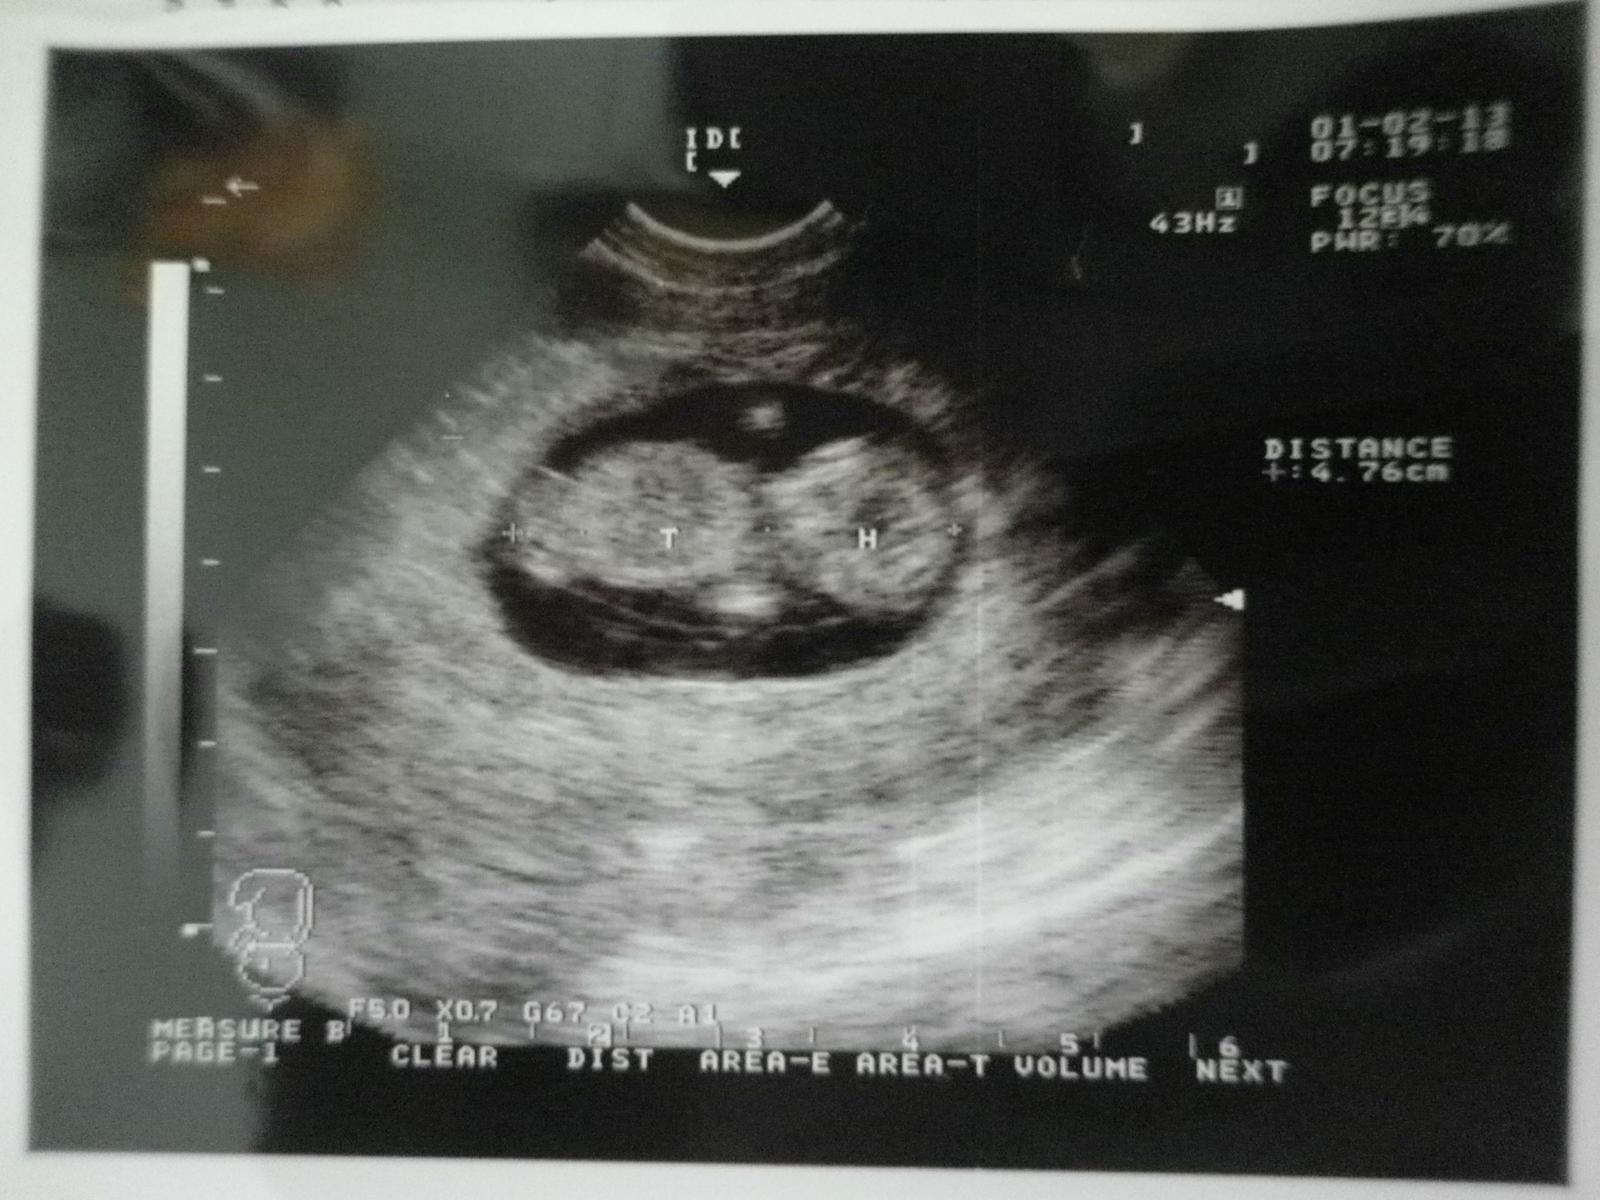

dnešná poradňa nedopadla moc dobre..dostala som lieky na udržanie tehotenstva kvôli tým bolestiam čo mávam...ale inak bábo je v úplnom poriadku..zodpovedáme 11+5tt,termíny máme 18. a 19. augusta..bábo má skoro 4,8 cm,srdiečko mu bije,má dve ručičky aj nožičky,stále sa vrtelo a aj NT máme v norme..ďalšia poradňa v 16tt,ak by bolesti neustúpili,tak aj skôr

@daniela7481 tak mi mame termin 19.8 a meranie bolo v stredu to sme boli 11+2 a mali sme 4,76 cm a vraj je vsetko o.k apotla tabuliek vraj 12 tyzden je to od 6-8 cm,ale naozaj sa to neda velmi porovnavat,kym je vsetko o.k tak par mm podla mna nie je az tak podstatny